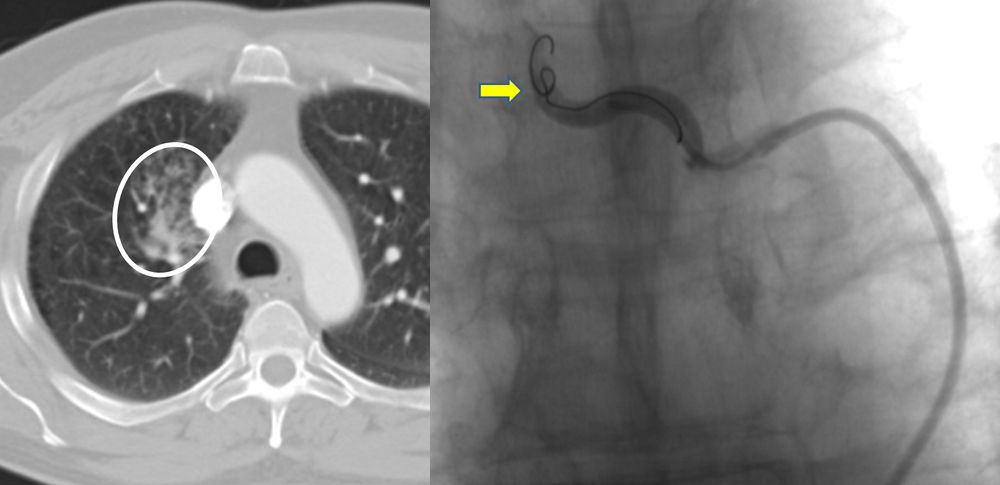

♦ Όγκους

Είτε προεγχειρητικά για την ελάττωση της αιμάτωσης του όγκου, είτε θεραπευτικά σε ορισμένες περιπτώσεις που δεν απαιτείται χειρουργείο ή υπάρχει αντενδειξη για χειρουργική αφαίρεση του όγκου.

Συνοπτικά υπό την καθοδήγηση του αγγειογράφου, αναγνωρίζεταιτο παθολογικό αγγείο-αγγεία και με ειδικούς καθετήρες και μικροκαθετήρες, διοχετεύονται εμβολικά υλικάόπως μικροσφαιρίδια ή coils, ώστε να αποφραχθεί ή να μειωθεί η παθολογική αγγείωση.